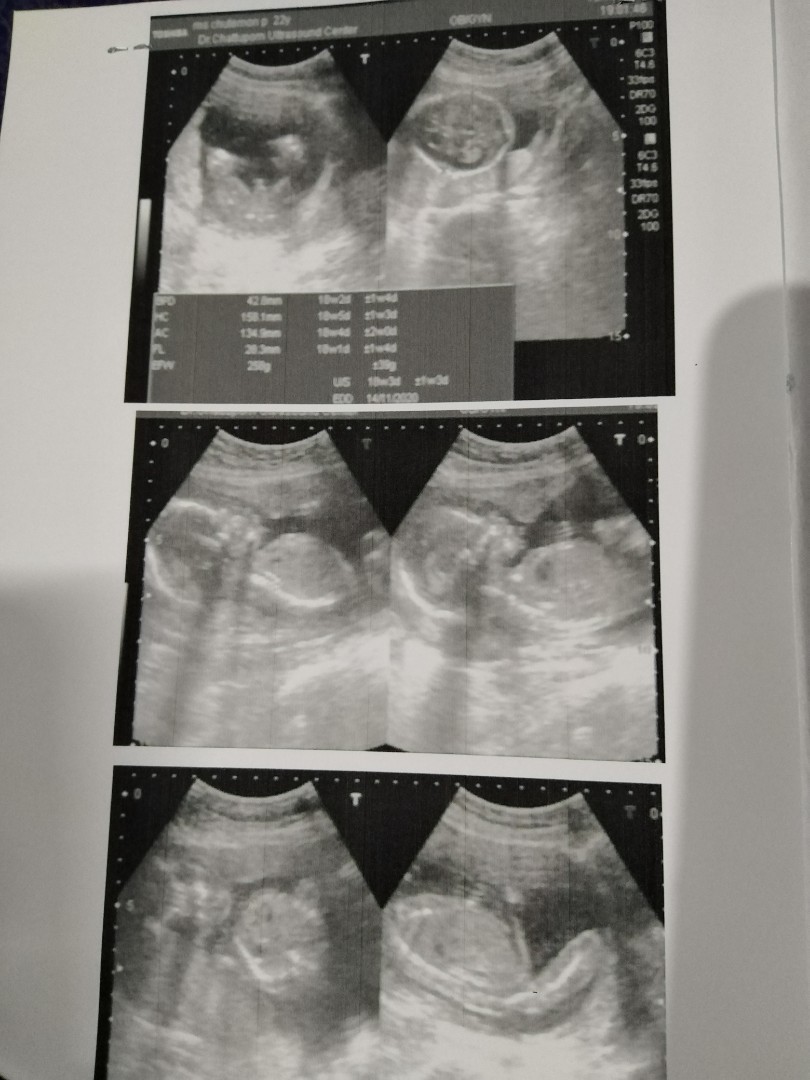

ขอดู รูปซาว หน่อยค่ะว่าเหมื่อนกันไหม หมอ บอกว่า เป็น ญ เพราะไม่มีจู๋โผลมา บ้านอื่น ได้ ญ แบบนี้หรือเปล่าค่ะ แม่แอบกังวล อยากได้ญ กลัว จู่ โผล่มาทีหลัง 😁23+4.

บ้านนี้หมอก็บอกผู้หญิง80%